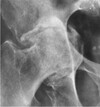

What are the radiographic signs of Paget's disease

Bones affected have a mottled, cotton-wool appearance (from irregular formation)

283

What pathology is seen here?

Paget's disease

284

Paget's disease (note cotton ball appearance)